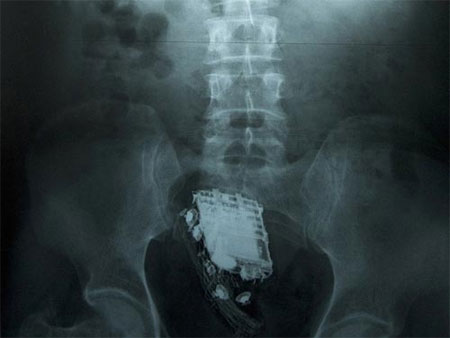

Default Hy hữu chuyện điện thoại kẹt vào "chỗ kín"

Roderick Bambury, một tù nhân đang bị giam giữ tại nhà tù Perth Prison, một trong những nhà tù được canh phòng nghiêm ngặt nhất tại Scotland, đã lâm vào tình trạng “dở khóc dở cười”, sau khi cố gắng nhét một chiếc điện thoại di động vào hậu môn với hy vọng có thể mang vào buồng giam nhưng lại không thể lấy chiếc điện thoại này ra ngoài.

Bambury sau đó đã phải trải qua một ca phẫu thuật khẩn cấp để lấy chiếc điện thoại di động ra khỏi cơ thể của mình.

Quy định của nhà tù Perth Prison là không cho phép các phạm nhân mang thiết bị liên lạc vào bên trong buồng giam. Tuy nhiên, tù nhân 36 tuổi đến từ thành phố Dundee (Scotland) thừa nhận đã sử dụng “mánh khóe” này để qua mặt các lính canh của trại giam và mang điện thoại di động vào buồng giam của mình từ tháng 6 năm ngoái.

Sau khi bị phát hiện hành vi gian lận, Bambury đã bị kết án tăng thêm 4 tháng rưỡi tù giam so với bản án phạt ban đầu.

Tuy nhiên, Bambury cũng đã rất “tử tế” khi gửi lời cám ơn đến đội ngũ bác sĩ đã giúp y thoát khỏi tình trạng khó chịu khi lấy chiếc điện thoại ra khỏi cơ thể, đồng thời chấp nhận án phạt tăng thêm dành cho mình mà không kháng cáo.